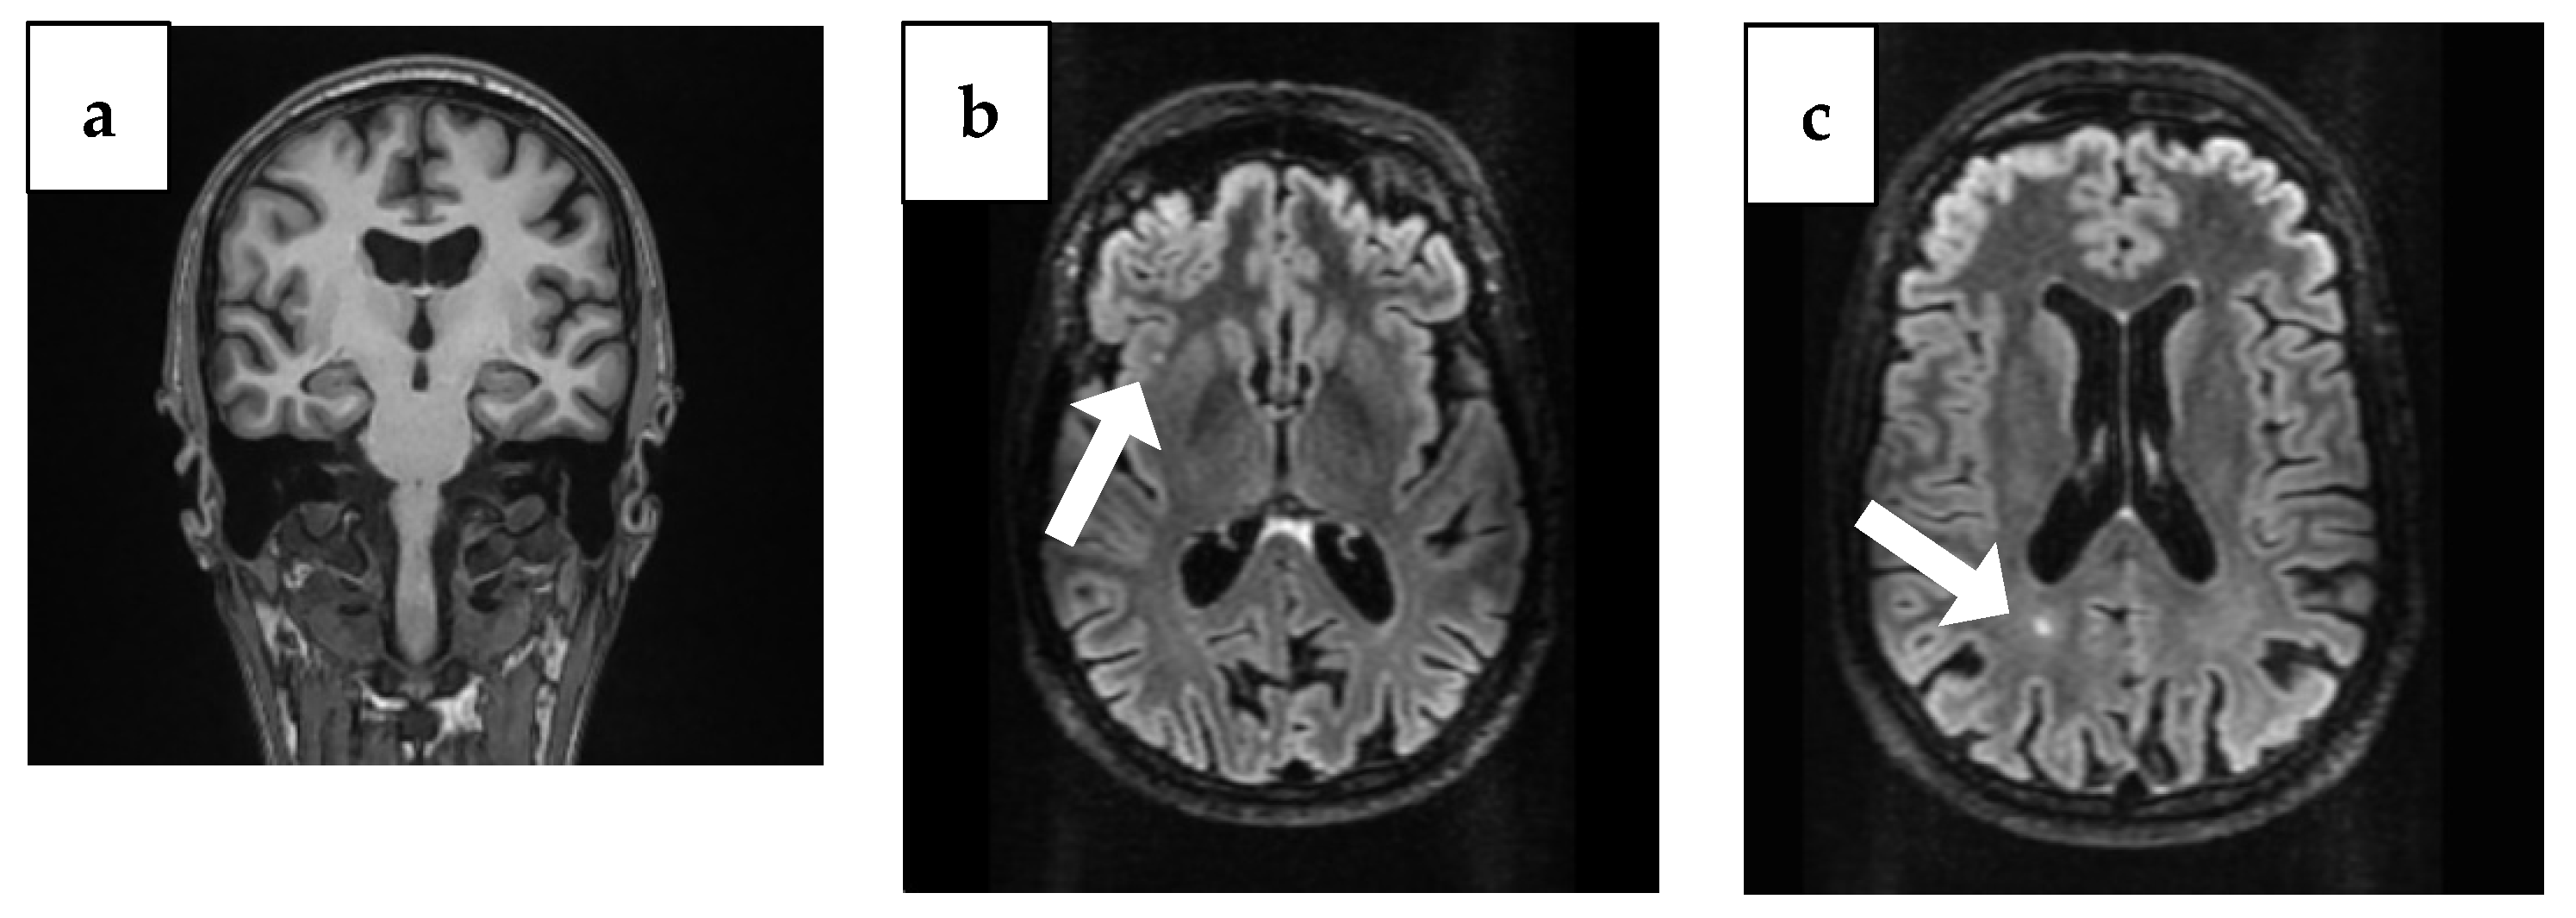

| Baseline (4 years ago) | MMSE 16/30 | Tau, p-Tau, Aβ42 within normal limits; 14-3-3 negative | Temporal atrophy; two punctiform FLAIR lesions (insula + occipital horn); ex vacuo ventriculomegaly | Initial cognitive decline after vestibular neuritis; onset of disorientation and working memory/language deficits |

| Year 3 (1 year ago) | MMSE 9/30, MoCA 4/30 | Tau ↑ 877 pg/mL; p-Tau ↑ 63.6 pg/mL; Aβ42 ↓ 0.94 | Hippocampal atrophy (MTA score 2); parietal atrophy (Koedam 2); severe corpus callosum thinning with splenium demyelination (T2/FLAIR hyperintensity, T1 hypointensity) | Severe cognitive disorder requiring permanent care; anxiety and depression prominent |